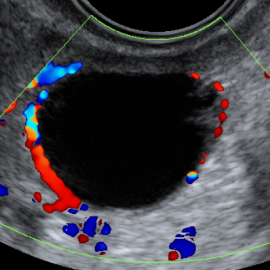

والتي يتم فيها تطبيق برامج تحريض الإباضة لمختلف تقنيات الإخصاب المساعد طبياً مع إجراء رصد للجريبات المبيضية ومراقبة تطورها، إضافة إلى دراسة بطانة الرحم والجريان الدموي ضمنها باستخدام الإيكو دوبلر الملون. وتم حديثا إضافة دراسة مشعر التعشيش أو الانغراس مع دراسة دوبلر الشريان الرحمي.